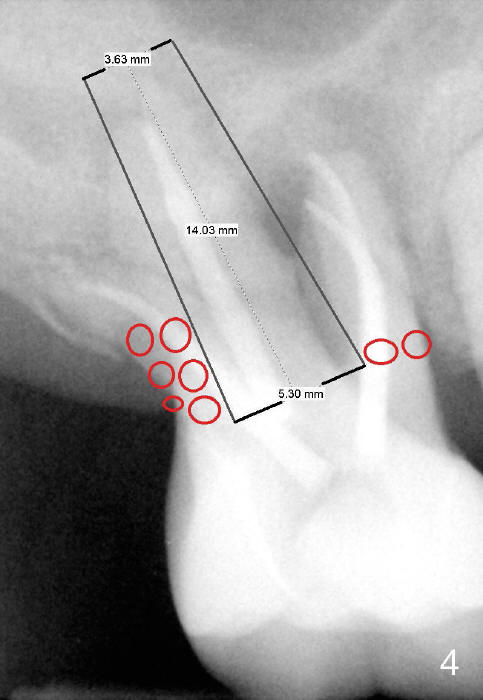

If the septum is basically intact, a 5.3x12 bone-level implant is placed in an ideal trajectory for restoration (Fig.3).  The mesial and distal margin of the implant is at the level of the alveolar crests (arrows); bone graft is placed evenly to cover the coronal threads (red circles). If the septum is defective to some degree, a longer implant is placed distally (Fig.4) with more bone graft placed distally.  Or the implant is placed deeper (Fig.5).  If the septum is severely defective, an extra wide, but shorter implant (6.9x10 mm bone-level SM) is used (Fig.6).  Or an extra wide UF implant with extra 2 mm length may offer better primary stability (Fig.6' (with sinus lift)).  The primary stability of the extra wide implants is derived from contact with the mesial and distal socket walls.